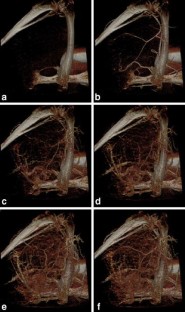

Flat-panel volume computed tomography (fpVCT) is a recent development in imaging. We discuss some of the musculoskeletal applications of a high-resolution flat-panel CT scanner. FpVCT has four main advantages over conventional multidetector computed tomography (MDCT): high-resolution imaging; volumetric coverage; dynamic imaging; omni-scanning. The overall effective dose of fpVCT is comparable to that of MDCT scanning. Although current fpVCT technology has higher spatial resolution, its contrast resolution is slightly lower than that of MDCT (5-10HU vs. 1-3HU respectively). We discuss the efficacy and potential utility of fpVCT in various applications related to musculoskeletal radiology and review some novel applications for pediatric bones, soft tissues, tumor perfusion, and imaging of tissue-engineered bone growth. We further discuss high-resolution CT and omni-scanning (combines fluoroscopic and tomographic imaging).